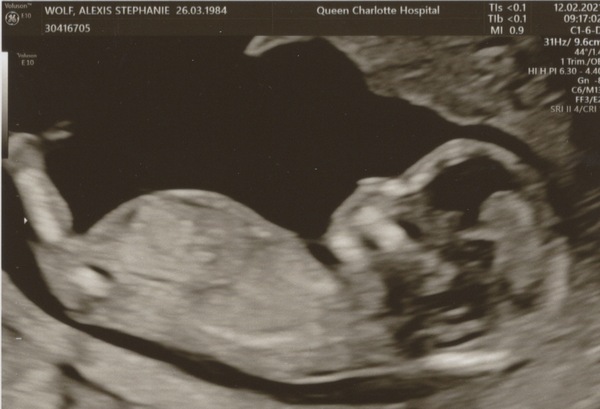

WolfMother326 · 12/02/2021 12:20

@PurplePansy05 thanks for your reply. I just had my scan and hadn't seen your message first. I brought the NIPT paperwork and the ultrasound technician took a copy of it and said I only needed the Nuchal Translucency unless I really wanted the blood test. I decided to skip it as the Nuchal looked really good and the NIPT tests were 1 in 10,000 chance for all categories. I feel ok about it!

Was so relieved and happy to see the baby again today. DH was able to come and it was quite emotional. Due date is now 17 August Flowers Apparently the baby has very long legs already, and we were told they're going to be tall!

Ah as long as you have the results in your notes it's all good @WolfMother326! Huge congratulations, what a beautiful photo 😊💛 xx

Lovely scan @WolfMother326!